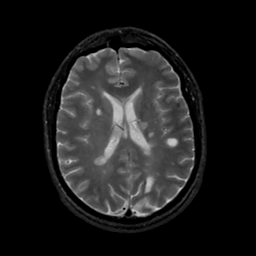

MR Study #15, June 9, 1991 -- Slice #30